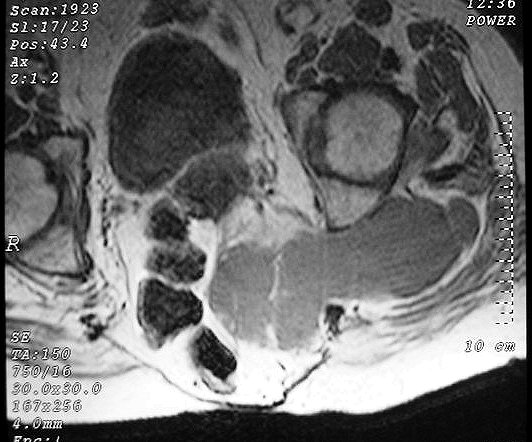

Сакральная хордома. Д-р Марсело Сенна Ксавье де Лима, Paul Roland Kaleff, и Антонио Рожерио del'Arco Roth Аугусто Варгас. Рецидив. Часть крестца была удалена ранее. Пнд, 27/11/2017 - 21:03 #1 Катенёв Валенти... Не на сайте Был на сайте: 7 лет 4 месяцев назад Зарегистрирован: 22.03.2008 - 22:15 Публикации: 54876 Внутричерепная хордома. http://pubs.rsna.org/doi/full/10.1148/rg.234025176 Пнд, 09/07/2018 - 20:44 #2 Катенёв Валенти... Не на сайте Был на сайте: 7 лет 4 месяцев назад Зарегистрирован: 22.03.2008 - 22:15 Публикации: 54876 Продолжение. Приложения: